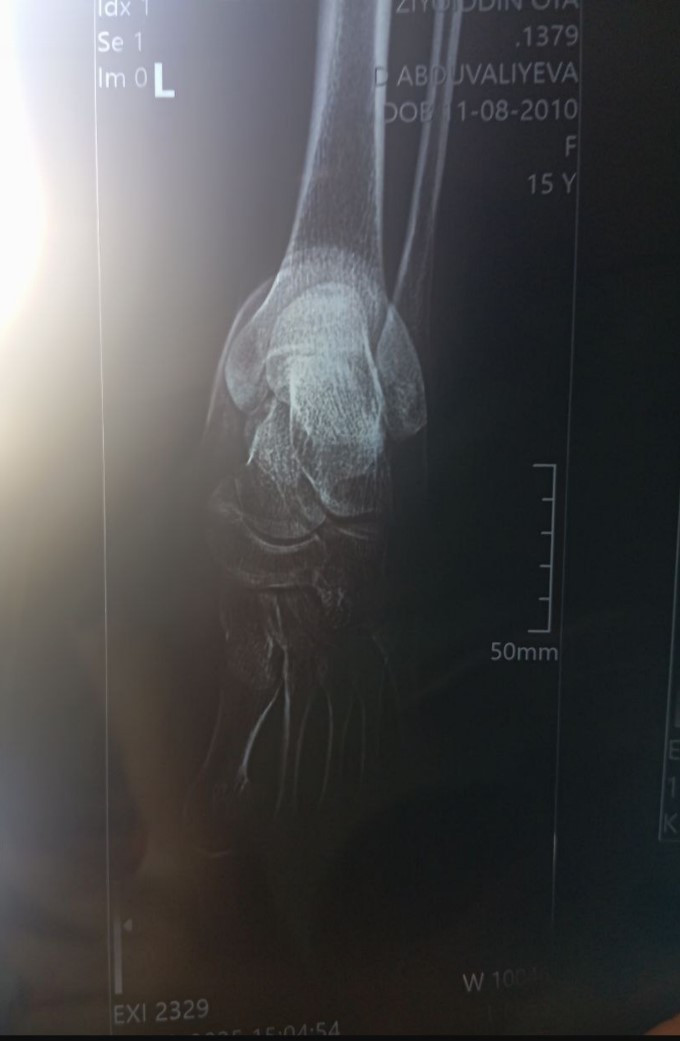

Добрый день! Помогите пожалуйста. Дочка 2 августа подвернула ногу, ходила прихрамывала говорила все хорошо. Через несколько дней нога опухла, показали врачам сказали есть трещина. Сказали ходить на костылях пару недель ногу не нагружать, перевезали эластичным бинтом. Пошла уже третья неделя дочка говорит что боли есть не сильные как раньше но есть.

Пожалуйста посмотрите прикрепленный рентген, может там что нибудь серьезное спасибо!

Здравствуйте. Из-за качества снимка (затемнение, блики, низкая чёткость, темный задний фон) рассмотреть линии перелома или чётко оценить суставные поверхности невозможно.